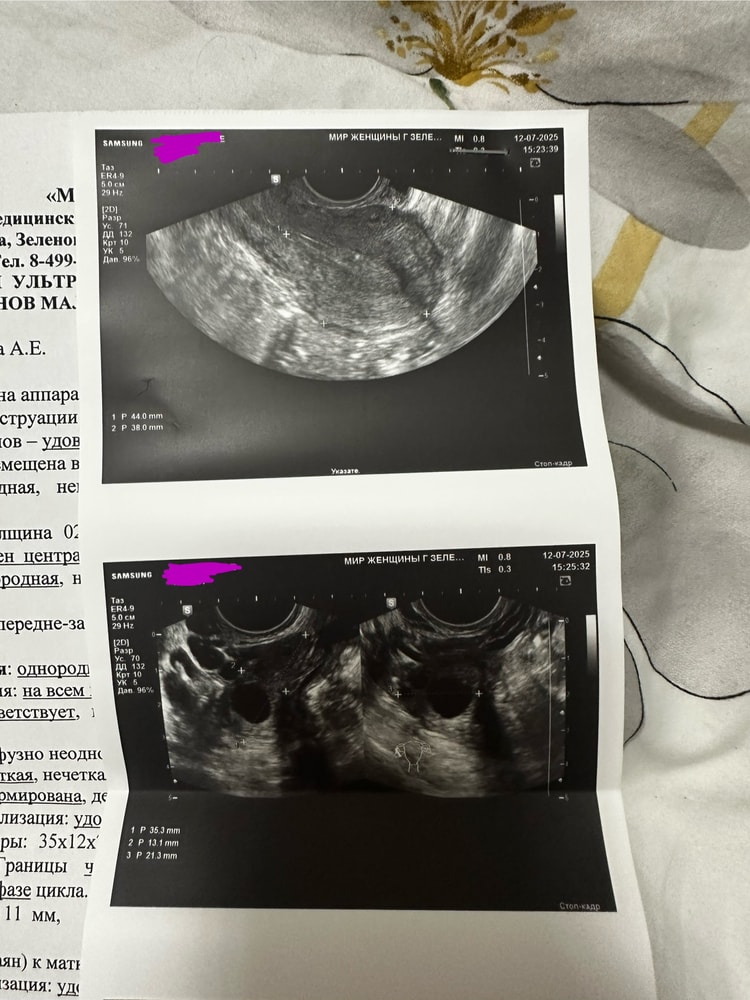

Пошла к гинекологу на 6дц, говорит сбой, но хгч сдаем на всякий, делаем сразу узи (тк в вс у меня был вылет в отпуск и я пошла получить добро на вылет). По узи картина начала цикла. Желтого тела нет, фолликулы и все, доминантного пока нет. В тот же день пересмотрела узи ещё у одного очень толкового врача на хорошем аппарате (фотку узи прикладываю). Все дало добро на вылет, мол начало цикла, беременность маловероятна.

Пришел блин!!! хгч 12,75 (у меня никогда не было ЕБ, я в шоке). Матка пустая, эндометрий никакой. Очень переживаю за внематочную, но там наверное должно быть желтое, и гравидарный (пушистый) эндометрий.